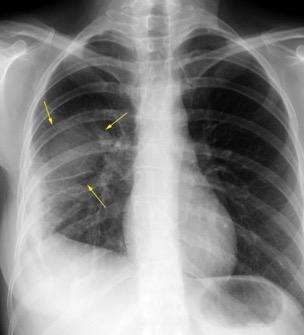

Neumonía a neumococos base izda. con derrame que aumenta.

Broncograma en lateral y en US.

(36-66% en ingresados)